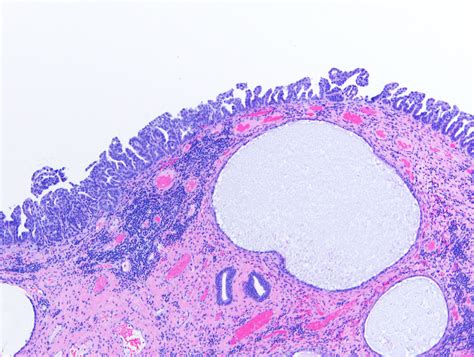

Receiving a diagnosis of Papillary Serous Carcinoma can be an overwhelming and life-altering experience. As a subtype of epithelial cancer that most commonly originates in the ovaries, fallopian tubes, or the peritoneum, it is characterized by its distinct cellular structure under a microscope, where the cells form small, finger-like projections known as papillae. Understanding the nature of this malignancy is the first step toward navigating treatment options, communicating with your medical team, and advocating for your own health journey. By breaking down the complexities of this condition, patients and caregivers can better grasp the diagnostic processes, treatment pathways, and the ongoing support structures available.

At its core, Papillary Serous Carcinoma is considered an aggressive form of cancer because it often presents at a later stage. Because the symptoms are frequently subtle—or even non-existent—in the early phases, the disease often spreads throughout the abdominal cavity before it is detected. The term "serous" refers to the fluid-producing cells from which the tumor arises, and "papillary" describes the architectural pattern of the cells.

• High-Grade Classification: Most cases are categorized as high-grade, meaning the cells look significantly different from normal cells.